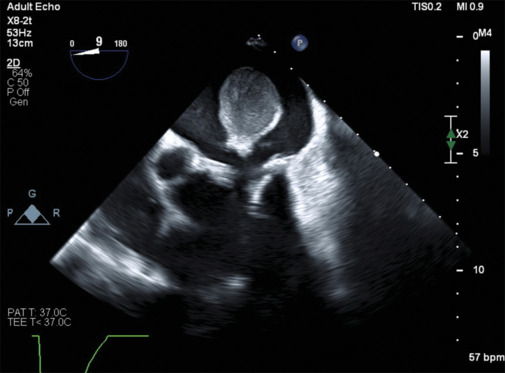

A 54-year-old patient with a medical history of hypertension, dyslipidemia, and diabetes underwent mitral valve replacement surgery with a biologic valve. During a chest computed tomography scan for breast neoplasia staging, a reduced luminal filling in the left atrium (3.6 cm) was unexpectedly found, prompting further cardiac evaluation. The patient was referred to the emergency department experiencing shortness of breath and fatigue, which improved after furosemide administration, and remaining stable throughout hospitalization. A transesophageal echocardiogram was performed the following day and revealed a biologic mitral valve prosthesis slightly displaced toward the left ventricle with an average transprosthetic gradient of 7 mmHg. Notably, a sizable intermediate echogenic mass measuring 3.0 cm × 3.5 cm was detected and attached to the prosthesis ring in a lateral and posterior position, within the left atrium. A mild degree of periprosthetic regurgitation was also noted. Given the substantial suspicion that the observed mass was a thrombus, the patient was commenced on anticoagulation therapy while awaiting cardiac magnetic resonance imaging for better characterization of the mass. Over 4 weeks, the thrombus notably decreased in size, disappearing entirely by the 6th week. This case highlights the significance of employing multiple imaging techniques in managing cardiac masses. The incidental discovery of the mass, its characterization, and subsequent management through anticoagulation, followed by confirmation and monitoring through echocardiogram, underscore the importance of a multimodal approach in diagnosing and treating such conditions.